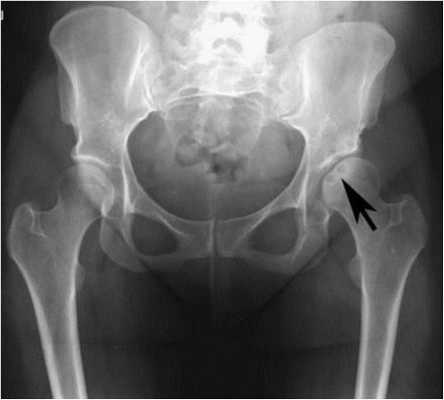

Рисунок 1. Рентгенограмма таза в передне-задней проекции. Рисунок 2. Рентгенограмма в боковой проекции при «позе лягушки» - бедро в положении 45° сгибания и максимальной наружной ротации. Рисунок 3. Рентгенограмма тазобедренного сустава в переднезадней проекции.

При рентгенологическом исследовании было выявлено значительное уплощение вертлужной впадины с сужением полости сустава и образованием околосуставных остеофитов.

Это пример вторичного остеоартрита тазобедренного сустава, что обусловлено:

- Молодым возрастом пациентки

- Полом пациентки

- Вовлечением левого тазобедренного сустава

- Рождением пациентки в ягодичном предлежании

- Отсутствием в анамнезе травмы или чрезмерной нагрузки на тазобедренный сустав.